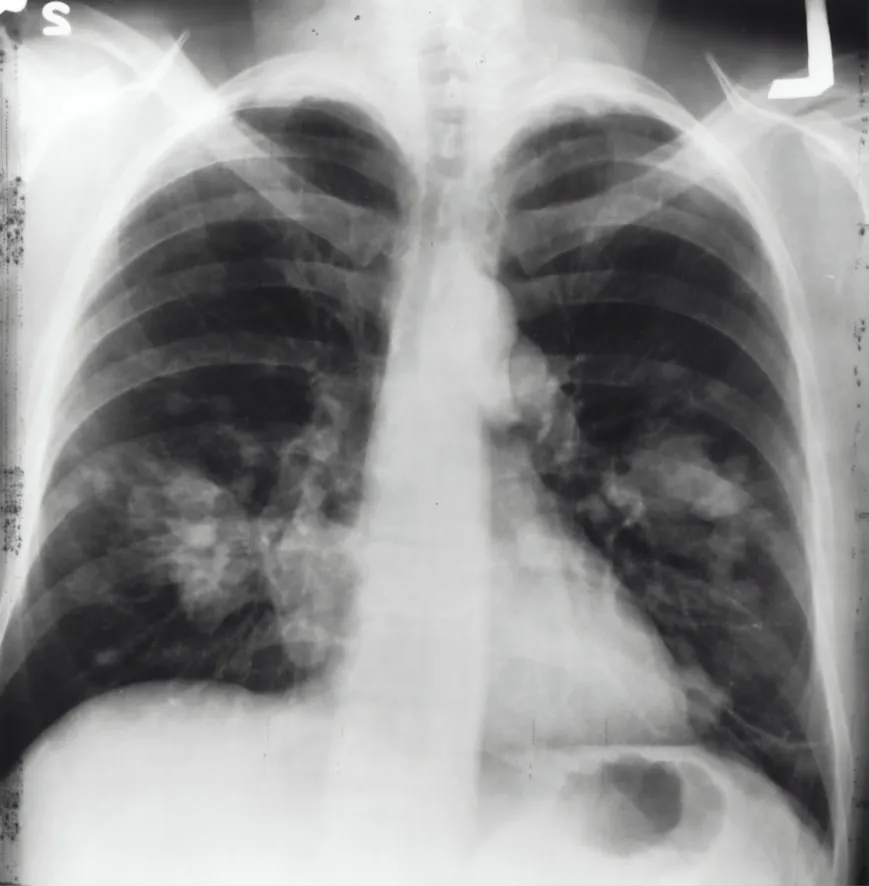

11. Plombage Surgery

National Cancer Institute on Unsplash National Cancer Institute on Unsplash

This tuberculosis treatment involved inserting balls or materials into the chest cavity to collapse a lung. While it sometimes helped the infection heal, it also led to severe complications and long-term health issues.